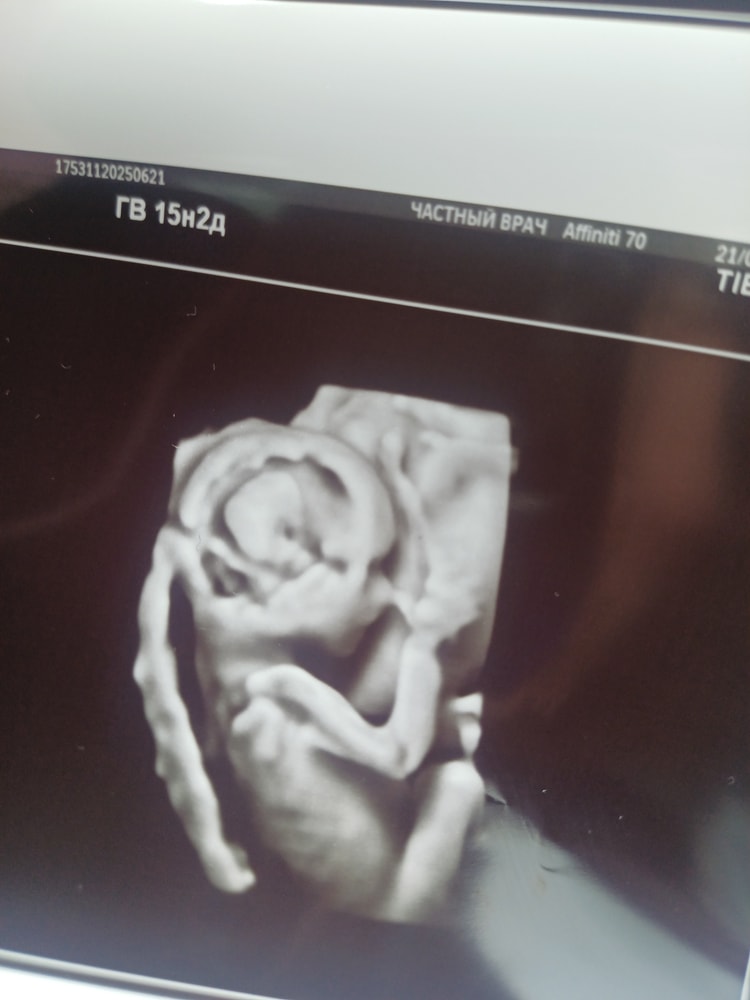

Странный вопрос задам 🌚, но на кого похож?

УЗИ, КТГ, доплерДевочка или мальчик?

Давайте без всяких « на таком сроке никто Вам не скажет » 🌚. Просто любопытно.

На 3 фото выглядит так, будто двойня🤣обман зрения такой, не сразу поняла)